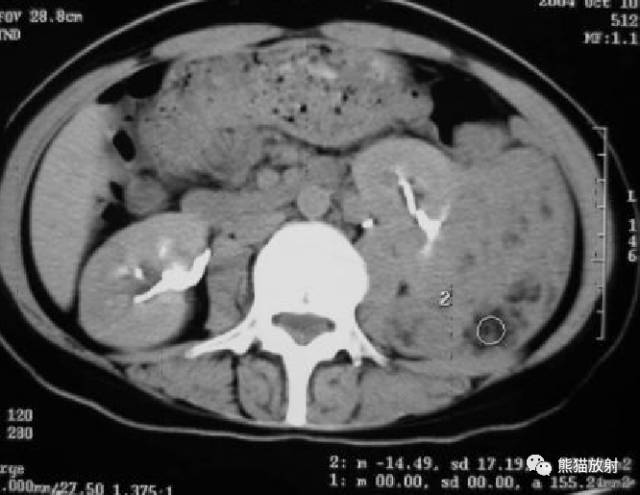

腹部CT:左肾中下极见不规则形肿块,内见多发分布斑片状脂肪密度影,肾盂肾盏受压、破坏。

③左肾肿块,内见明确脂肪密度。